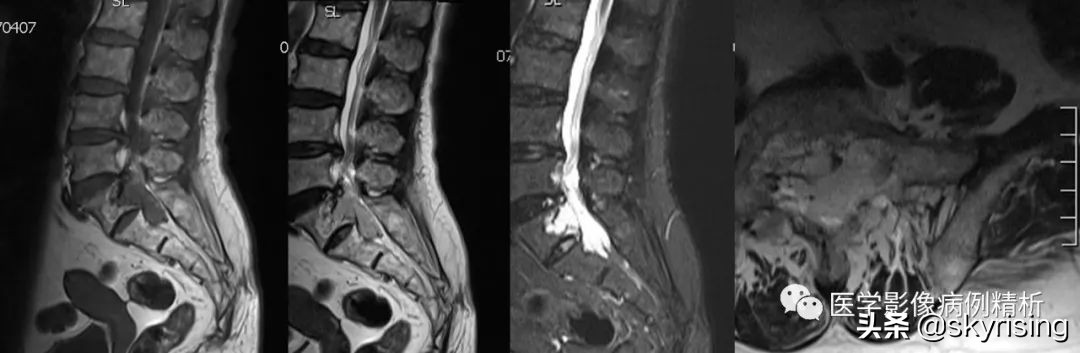

MRI平扫对比图

如图所示,红色箭头可见不规则形异常信号,轴位呈哑铃型,病灶前缘侵及骶1、2椎体后缘,绿色箭头见骨质局部破坏,病灶T1低信号,T2稍高信号,压脂像明显高信号,信号尚均匀,腰4-5、腰5骶1椎间盘向后方突出,硬膜囊受压,蓝色箭头可见腰4-5椎间盘后缘纤维化小点状T2高信号,提示纤维环后缘撕裂。本例骶1-2椎间盘形成,骶1椎体腰化不完全。

如图所示,分别为T1WI增强矢状位、冠状位、轴位,T1WI增强矢状位与T2WI压脂像非常相像,注意椎管内脑脊液信号,T1WI增强为低信号与T2WI压脂像高信号正好相反。红色箭头所示病灶明显强化,呈亮灯征感觉,清晰显示病灶范围,绿色箭头所示为病灶侵及骶1椎体后缘形成不规则形骨质破坏区。

红色箭头:病灶位于骶1-2椎体水平,轴位呈哑铃型,CT见骶1-2椎体后缘受侵、骨质破坏;MRI见病灶主体沿骶管及双侧骶孔生长,以左侧骶孔为著,T1低信号,T2稍高信号,压脂像高信号,接近脑脊液信号。

绿色箭头:骶1-2椎体后缘见信号向内部侵犯,边缘毛糙。

绿色箭头:腰4-5、腰5骶1椎间盘向后方突出,硬膜囊受压,蓝色箭头可见腰4-5椎间盘后缘纤维化小点状T2高信号,提示纤维环后缘撕裂,需警惕未来椎间盘脱出可能。